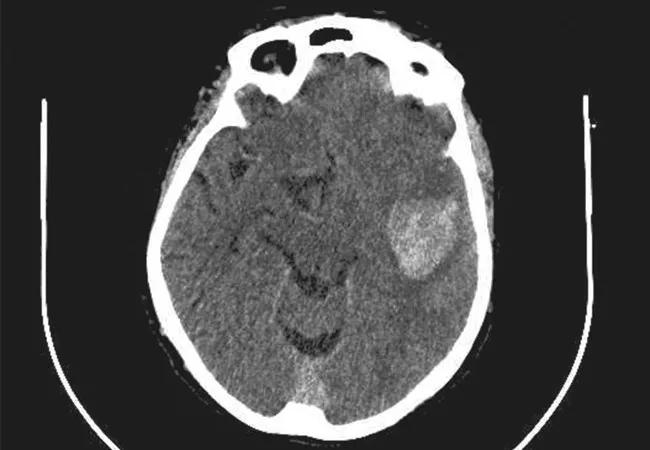

Can early surgical hematoma evacuation in intracerebral hemorrhage (ICH) be done in such a minimally invasive fashion that it promises significantly more benefit than risk?

That’s what Cleveland Clinic and nine other major U.S. medical centers hope to find out by participating in the Early Minimally Invasive Removal of Intracerebral Hemorrhage (ENRICH) study, a phase 3 clinical trial comparing a novel surgical system for clot removal within 24 hours of a hemorrhagic stroke to standard medical management. The system involves specialized devices designed to be manipulated through a small opening in the skull for gentle evacuation of the hematoma with minimal tissue damage.

“Historically, surgery was not a viable option for intracerebral hemorrhage because of damage caused by the surgery itself,” says Mark Bain, MD, a staff neurosurgeon in Cleveland Clinic’s Cerebrovascular Center who’s serving as the site’s principal investigator for the trial. “The system tested in ENRICH offers a minimally disruptive approach to the hematoma, fine control, and a gentle way to remove the hemorrhage. We have high hopes it will prove to be a better treatment for these devastating strokes.”

ICH is the most lethal form of stroke, resulting in death in one-third to one-half of victims and grave disability in many survivors. Following a sudden bleed in the brain, primary injury occurs within minutes to hours because of mechanical damage, oxygen loss, swelling and tissue death. Over the ensuing days, the trapped blood clot causes a host of secondary problems by releasing multiple factors that lead to inflammation and further tissue destruction.

Although it’s long been thought that surgical hematoma removal at the time of stroke could prevent damage, technical problems have proved daunting. Previous surgical trials have often demonstrated no benefit from surgical intervention when compared with a “wait and see” medical strategy, Dr. Bain explains.